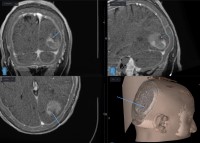

- Pre-Op